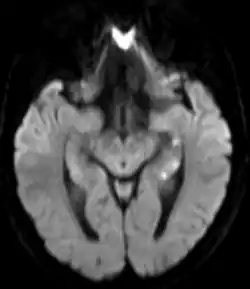

In erster Linie wurde eine transiente Durchblutungsstörung vermutet. Bei der Mehrzahl der Patienten lassen sich in der Magnetresonanztomographie punktförmige Diffusionsstörungen im lateralen Hippocampus nachweisen. Dagegen spricht jedoch, dass die transiente globale Amnesie im Gegensatz zu anderen kurzzeitigen Ischämien des Kopfes (TIA, Amaurosis fugax) kein Risikofaktor für das Erleiden eines Schlaganfalls ist.